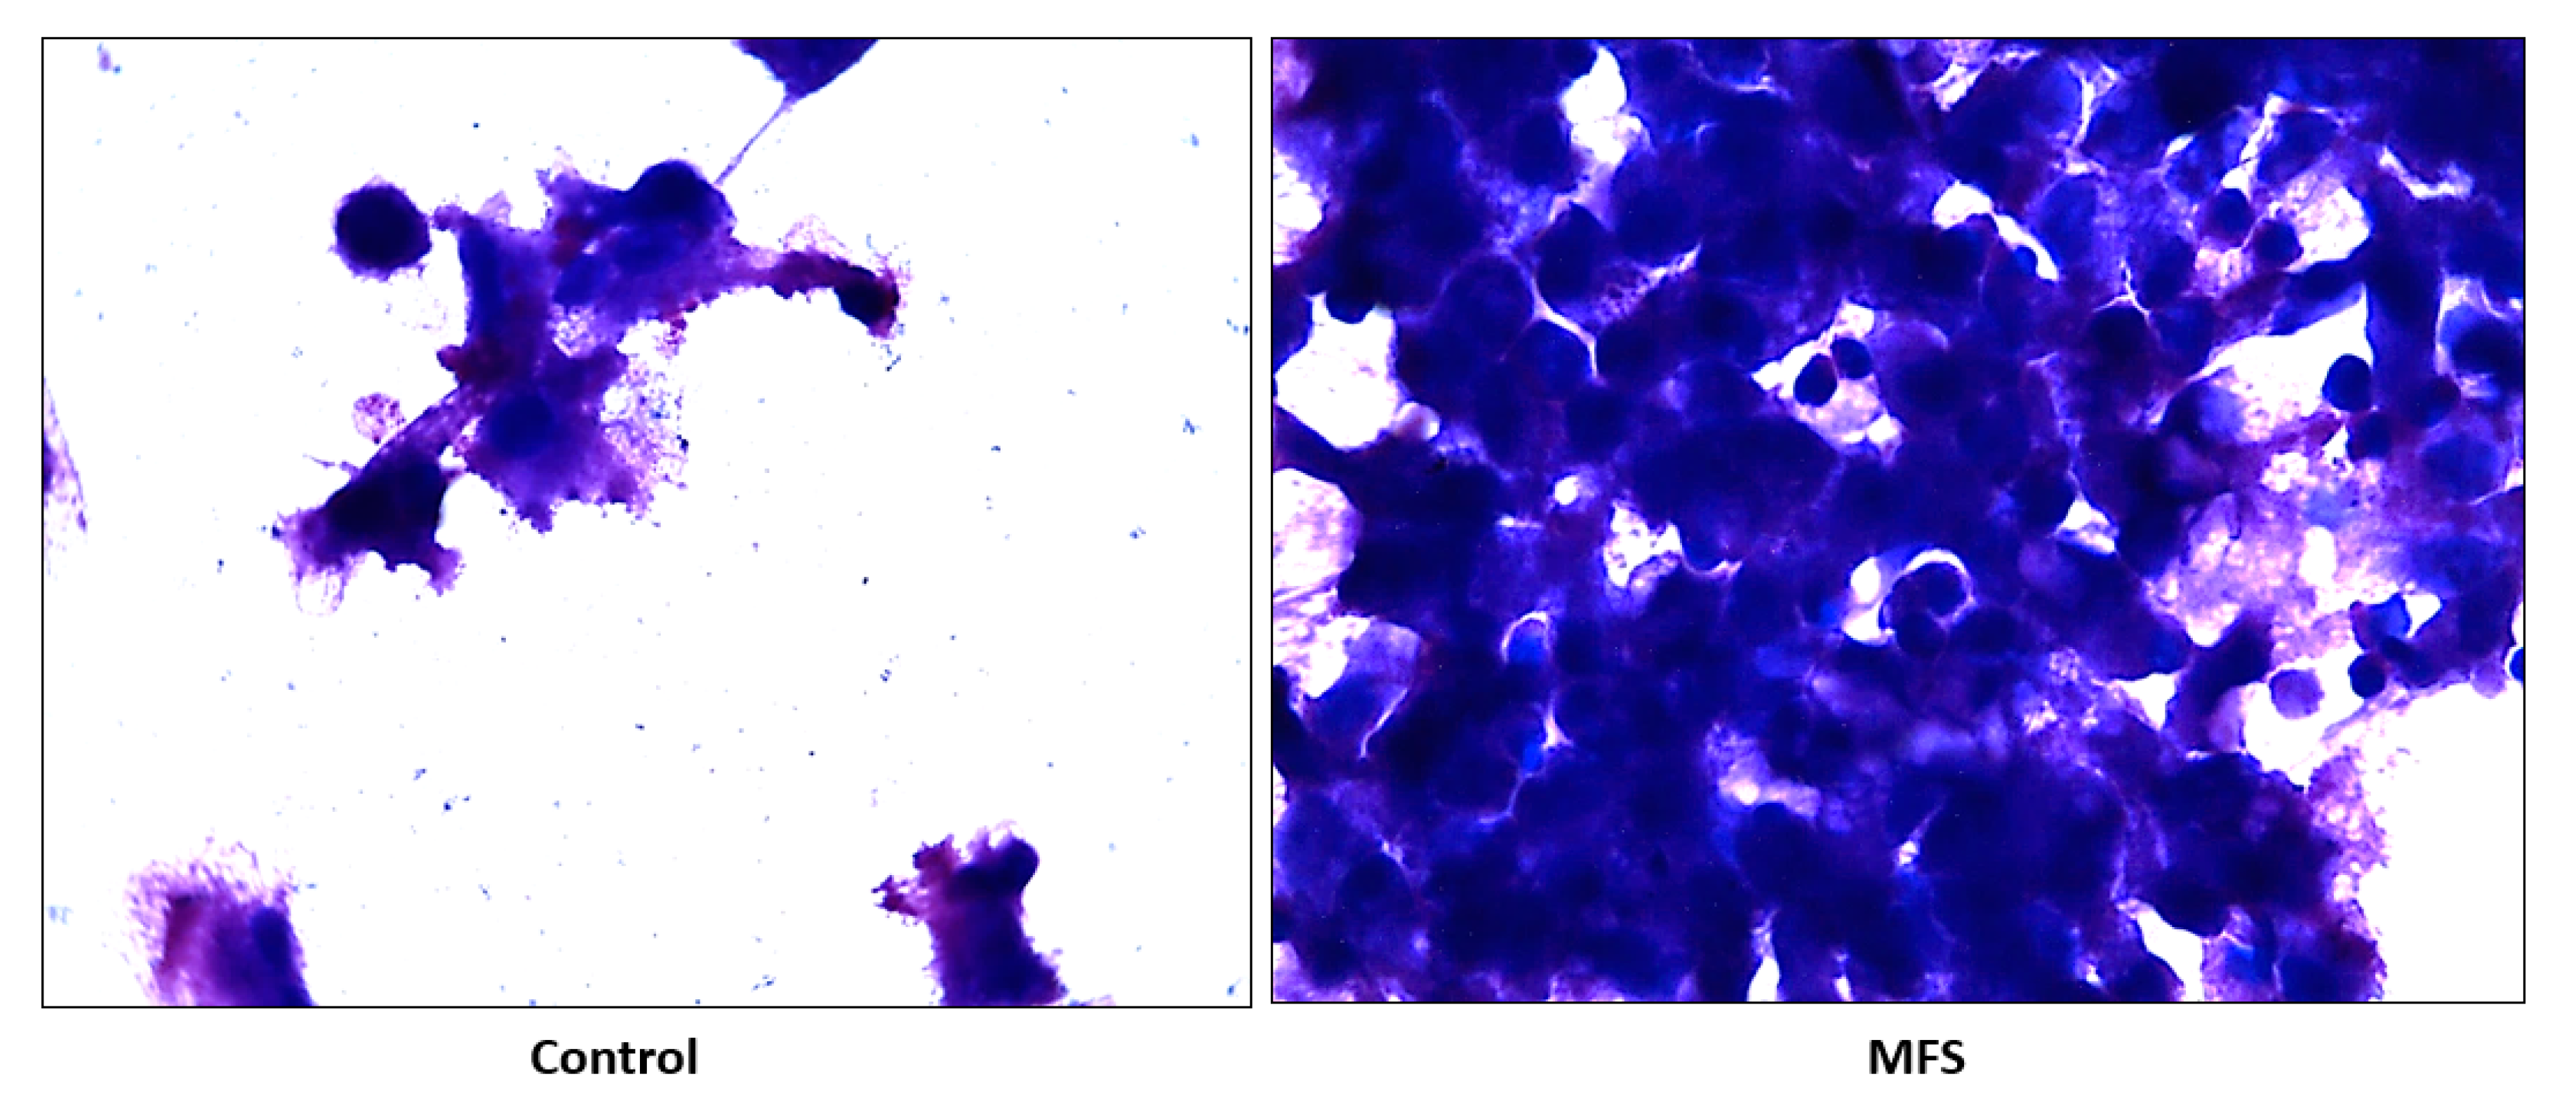

2.2. Hematoxylin and Eosin Staining of THP-1 Cells

Hematoxylin and Eosin (H&E) staining of THP-1 macrophages showed an increase in cell quantity after MFS treatment versus the sham-treated after 12 days of infection (Figure 2). These data indicate that THP-1 macrophage viability was enhanced after MFS treatment.

H&E staining of Mtb infected peripheral blood mononuclear cells (PBMCs) illustrates an increase in cell survival with MFS administration versus sham treatment after 15 days of infection (Figure 2), as well as an increase in cell density/aggregation and granuloma formation (Figure 6).

Figure 2. Hematoxylin and Eosin staining of untreated and MFS-treated samples of THP-1 cells. Microscopy work was done under 100×.

Subsequently, we measured the effects of 12 days of MFS treatment on Mtb infected human macrophages derived from THP-1 monocytes. MFS supplementation compared to the control condition over a 12-day period improved the viability of the human THP-1 cells as depicted by the H&E imaging, which portrayed a greater cell magnitude (Figure 1). This suggested that Mtb infection became too vigorous for the THP-1 cells to retain and secure in the absence of MFS prophylactic treatment. This conclusion is further supported by the data represented in Figure 2, which illustrates that after 12 days MFS treatment resulted in a statistically significant bacterial reduction compared to the sham-treated control. These results support the findings of Anand et al. [14] who showed that the green tea flavonoid EGCG inhibited Mtb survival within macrophages. This research group showed that EGCG down-regulated host molecule tryptophan-aspartate containing coat protein (TACO) gene transcription, thus influencing phagosome maturation and the capacity to contain Mtb.

The influence of MFS on Mtb infected PBMCs collected from eight healthy individuals was similar to the findings from the THP-1 macrophage assays. The H&E data showed enhanced PBMC cell viability, cell aggregation/density, and enriched granuloma formation after MFS treatment (Figure 6). This is significant because augmented granuloma development is linked to increased bacterial containment and improved host protection [19]. As with the THP-1 macrophages, the increased immune cell viability observed subsequent to MFS treatment coincided with a strong reduction in bacterial density among the infected PBMCs (Figure 2 and Figure 6). Taken together with the GSH and cytokine data, these results support direct MFS-related mycobactericidal effects and immunomodulation from granuloma formation and the trend for increased IL-12 and IFN-γ cytokine production (Figure 8, Figure 9, Figure 10 and Figure 11). Both IL-12 and IFN-γ are prominently involved in immune cell differentiation and activation in response to combating Mtb infection, a process linked to granuloma formation [20].